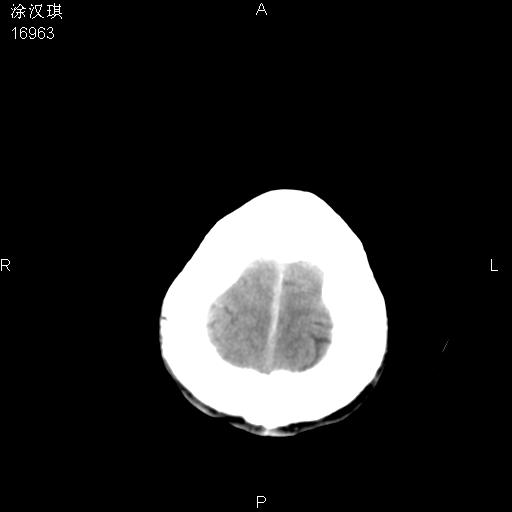

以下是引用chinazhouhua在2008-5-1 12:06:00的发言:[br]影像上来看,这是个典型的硬膜下血肿,包括右侧额颞部、大脑镰下、小脑幕下,而且在右侧额颞顶枕部、大脑镰下没看到高密度出血向脑沟内延伸,但是小脑幕下硬膜下有时候和蛛血不是很好鉴别,而且硬膜下很多时候伴有蛛血,往往在复查的时候出来,所以这种病人还是应该考虑硬膜下血肿伴有蛛血。

以下是引用zsl6918在2008-5-1 15:34:00的发言:[br]本病例主要表现为急性硬膜下血肿。